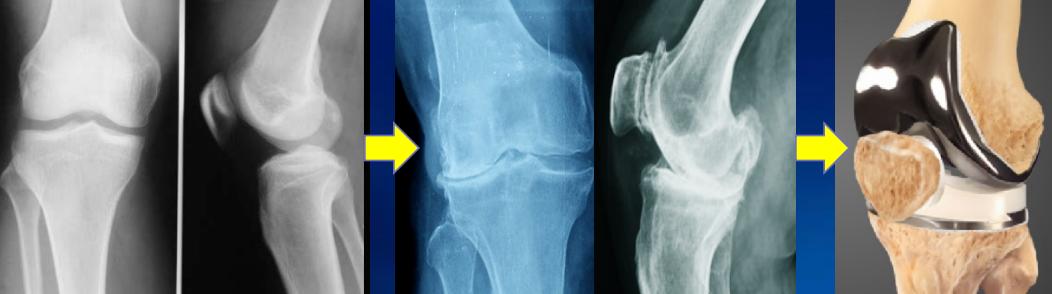

如果半月板因为损伤而被迫全部切除,是不可能再生的,膝关节面的软骨将会因失去半月板的保护而加速退变,骨性关节炎会提早发生,严重时就要换人工关节。

外侧半月板切除后关节磨损加速

因此,如果半月板损伤,应该积极的治疗,对于3度半月板损伤,无法通过保守治疗而痊愈的,必需积极的手术治疗才有机会重新愈合。